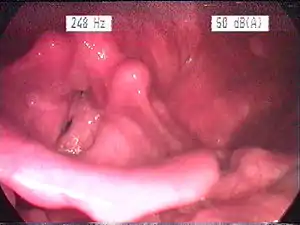

| Endoscopic image of an inflamed larynx caused by acid reflux | |

The larynx itself will often show erythema (reddening) and edema (swelling). This can be seen with laryngoscopy or stroboscopy (method depends on the type of laryngitis).[7]:108 Stroboscopy may be relatively normal or may reveal asymmetry, aperiodicity, and reduced mucosal wave patterns.[16]

Other features of the laryngeal tissues may include

- Redness of the laryngeal tissues (acute)

- Dilated blood vessels (acute)

- Thick, yet dry laryngal tissue (chronic)

- Stiff vocal folds

- Sticky secretions between the vocal folds and nearby structures (the interarytenoid region)